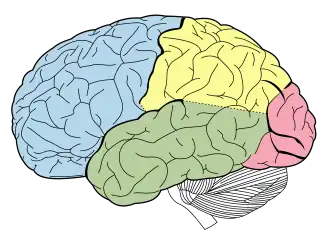

O telencéfalo inclui, entre outros, o lobo frontal (azul), parietal (amarelo), temporal (verde) e occipital (rosa). O cerebelo (branco) não faz parte do telencéfalo.

O Telencéfalo forma a maior porção do encéfalo. Juntamente com o Diencéfalo, constitui o Prosencéfalo durante o desenvolvimento embrionário. O telencéfalo compreende os dois hemisférios cerebrais, direito e esquerdo, incompletamente separados pela fissura longitudinal do cérebro.

Os hemisférios cerebrais apresentam 3 faces: Supero-externa, Interna e inferior. Cada hemisfério encontra-se ainda dividido em seis lobos, separados por sulcos principais: lobo frontal , parietal , temporal, occipital, lobo da insula e lobo do corpo caloso

Cada hemisfério apresenta 5 lobos:

- lobo frontal

- lobo parietal

- lobo temporal

- lobo occipital

- lobo da insula

Estes lobos possuem aproximadamente a mesma área em ambos os hemisférios cerebrais: por vezes, no entanto, podem existir certas áreas num hemisfério e não noutro. Esta situação relaciona-se com o conceito de dominância hemisférica, sendo o hemisfério esquerdo usualmente o dominante.